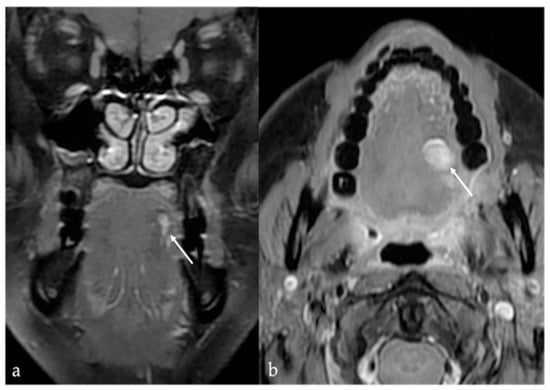

3. Schwannoma

| Schwannoma [6,7] | CT: hypodense MRI: high T2 SI, split fat, target and fascicular signs | Venous malformation, dermoid cysts, lipoma |